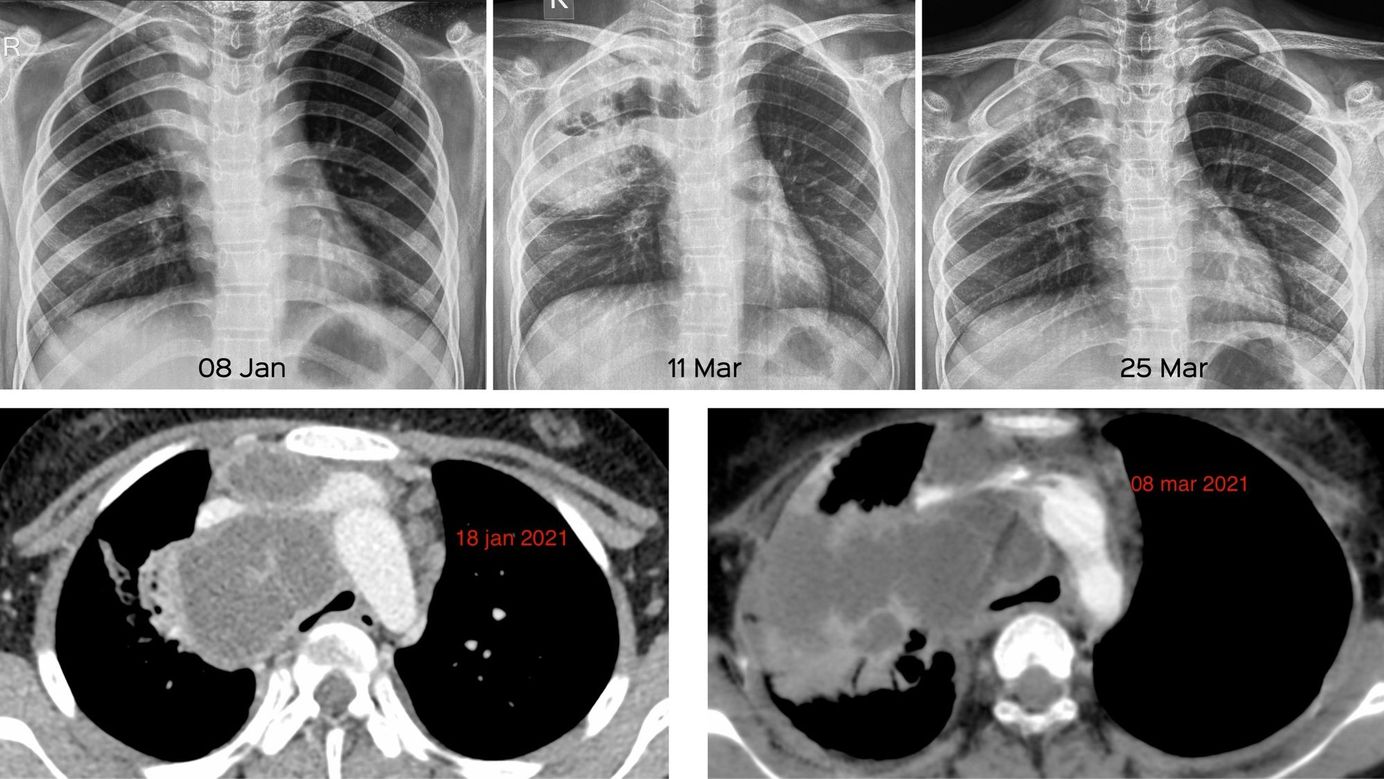

Case 8: Rupture of a Mediastinal Node into the Lung Members Public

14-years old girl with a large, tuberculous, necrotic right paratracheal mediastinal node that ruptured into the lung.

Bhavin Jankharia

Mediastinum